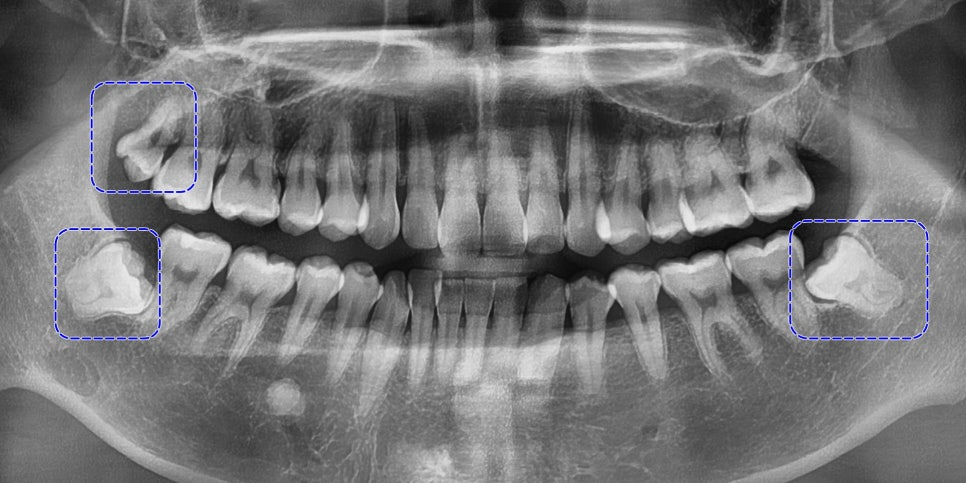

엑스레이를 분석해 보았을 때는

남아 있는 사랑니는 3개로

위턱 왼쪽에만 없었습니다.

23.11.24

위아래 어금니 간 폭경의 비율이

부조화를 보인 것을 볼 수 있습니다.

더불어, 왼쪽 비강의 협착과

상악동 염증 소견이 보입니다.